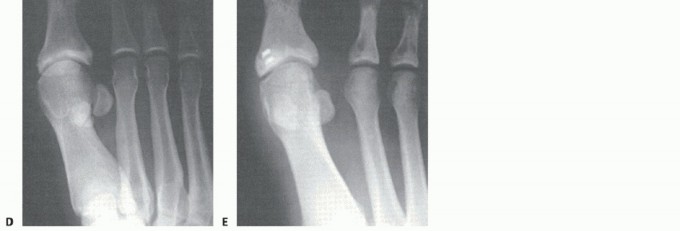

A thorough radiographic evaluation is mandatory (including weight-bearing views of the foot in the

anteroposterior [AP], lateral, and oblique planes) (FIG 3). Sesamoid axial views may also be helpful. Bilateral standing AP views are mandatory for comparison. Sesamoid station is assessed.

Forced (stress) dorsiflexion lateral views are helpful to diagnose disruption/diastasis of a bipartite sesamoid or a sesamoid fracture (FIG 4). It will also suggest a complete distal disruption of the FHB if the sesamoid(s) fails to migrate distally with dorsiflexion of the hallux. Studies suggest that more than 10.4 mm from the tip of the tibial sesamoid to the phalanx or more than 13.3 mm from the fibular sesamoid equates to a 99.7% chance for

plantar complex rupture.11 Compare the injured to uninjured side.